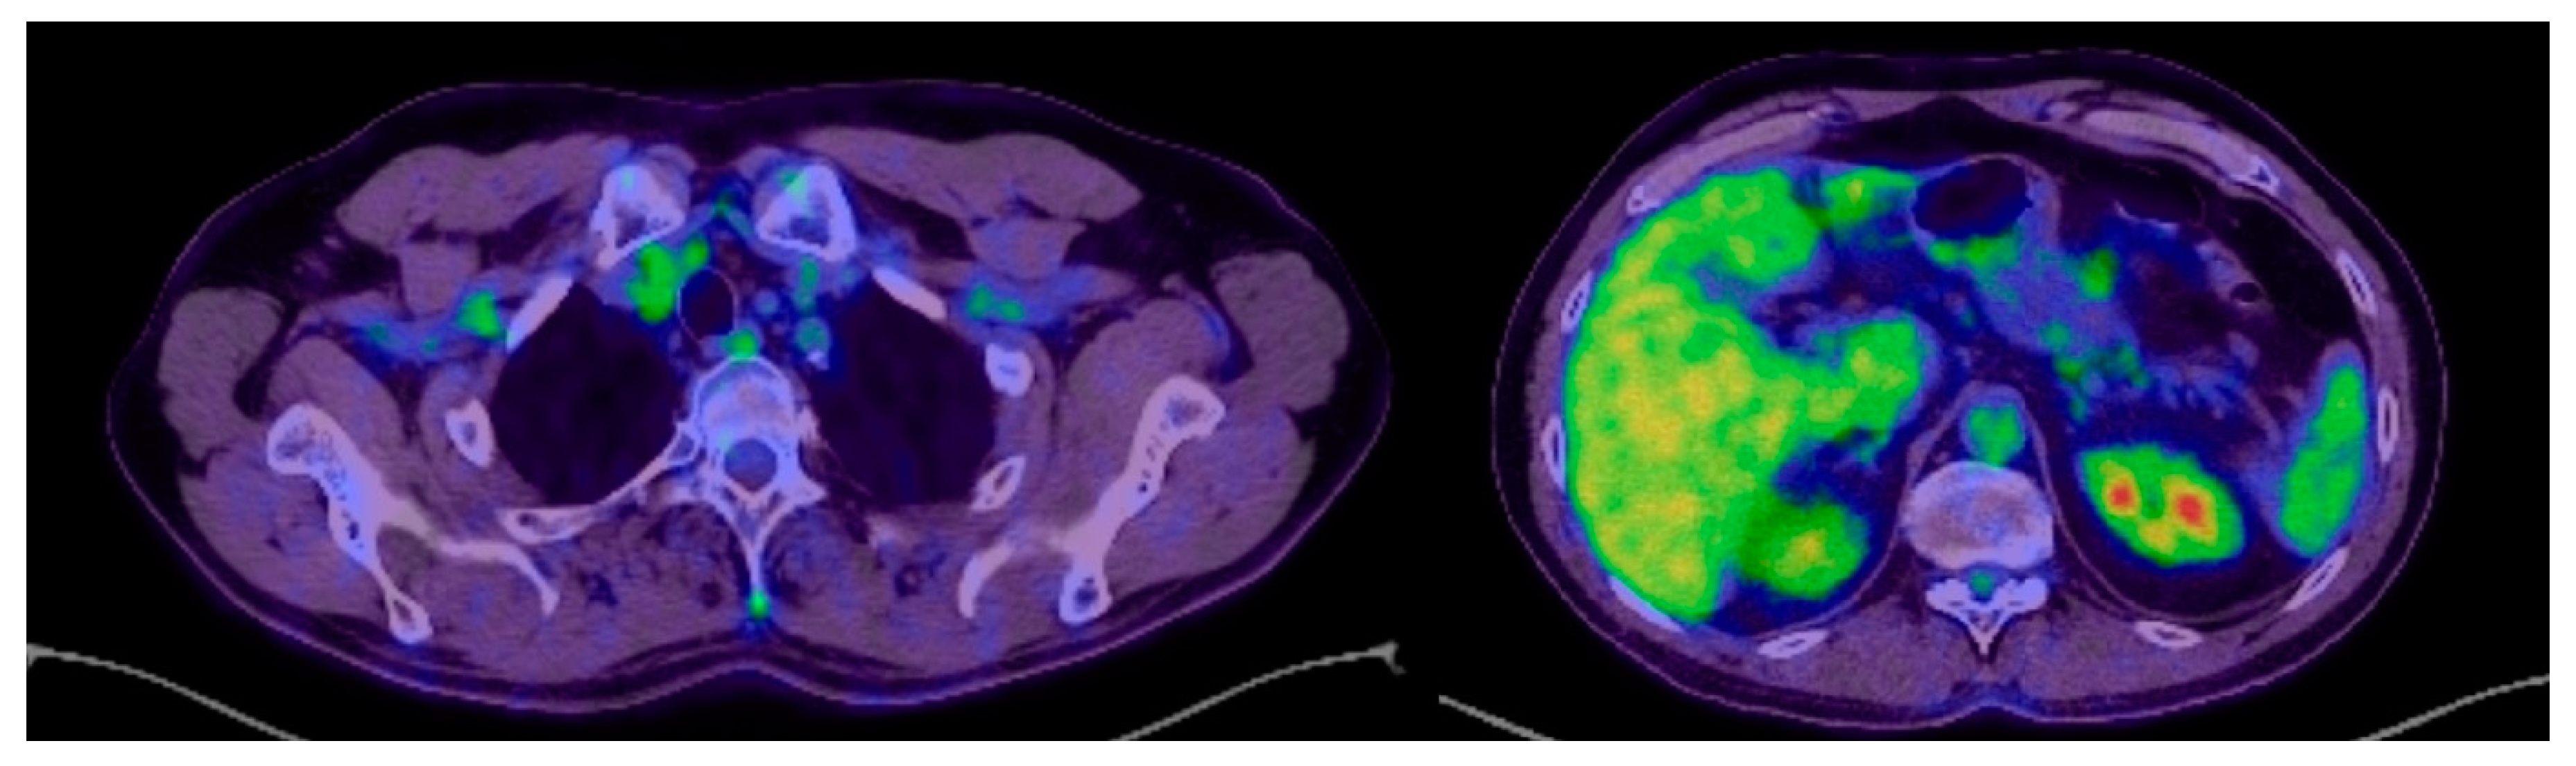

2. Case Report